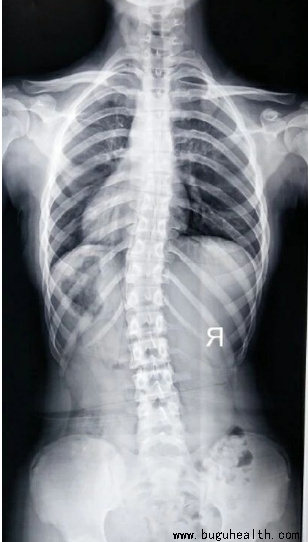

脊柱侧弯是脊柱的非正常弯曲。正常的脊柱在肩部有向后的弯曲,而在腰部有向前的弯曲。典型的脊柱侧弯包括三维的脊柱和肋骨畸形。根据度数的变化,脊柱从侧面弯曲,有时椎骨有轻微旋转,导致髋部或肩部出现不平衡。.....

如今,脊柱侧弯已经成为一个普遍性的问题。据统计,目前我国脊柱侧弯患者超300万,并以每年30万的速度递增,其中超过半数为青少年。脊柱侧弯成为继肥胖症、近视之后,我国儿童青少年健康的第三大“杀手”。要知道,脊柱侧弯不仅影响体型,更重要的是会导致严重的身体健康问题。.....

你知道吗?!继肥胖、近视后,脊柱侧弯已成为危害我国儿童青少年健康的第三大“杀手”。.....